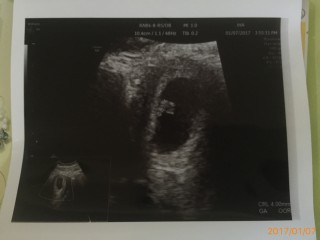

写真:6w6d:ふぅさん

4回目の妊娠です¨̮ 長男と長女の間に稽留流産してしまった子が居て エコーで見るまで不安でした… 検診予定日はまだ先でしたが茶オリや腹痛があり心配で受診。 心拍確認できて少しだけホッとしました。 現在は7w4dになってて茶オリも無くなってるので次の検診まで無事育ってくれていることを願うのみです☆*° 上の子達の時もこちらに投稿させてもらったので見返して成長を楽しみにしてます¨̮